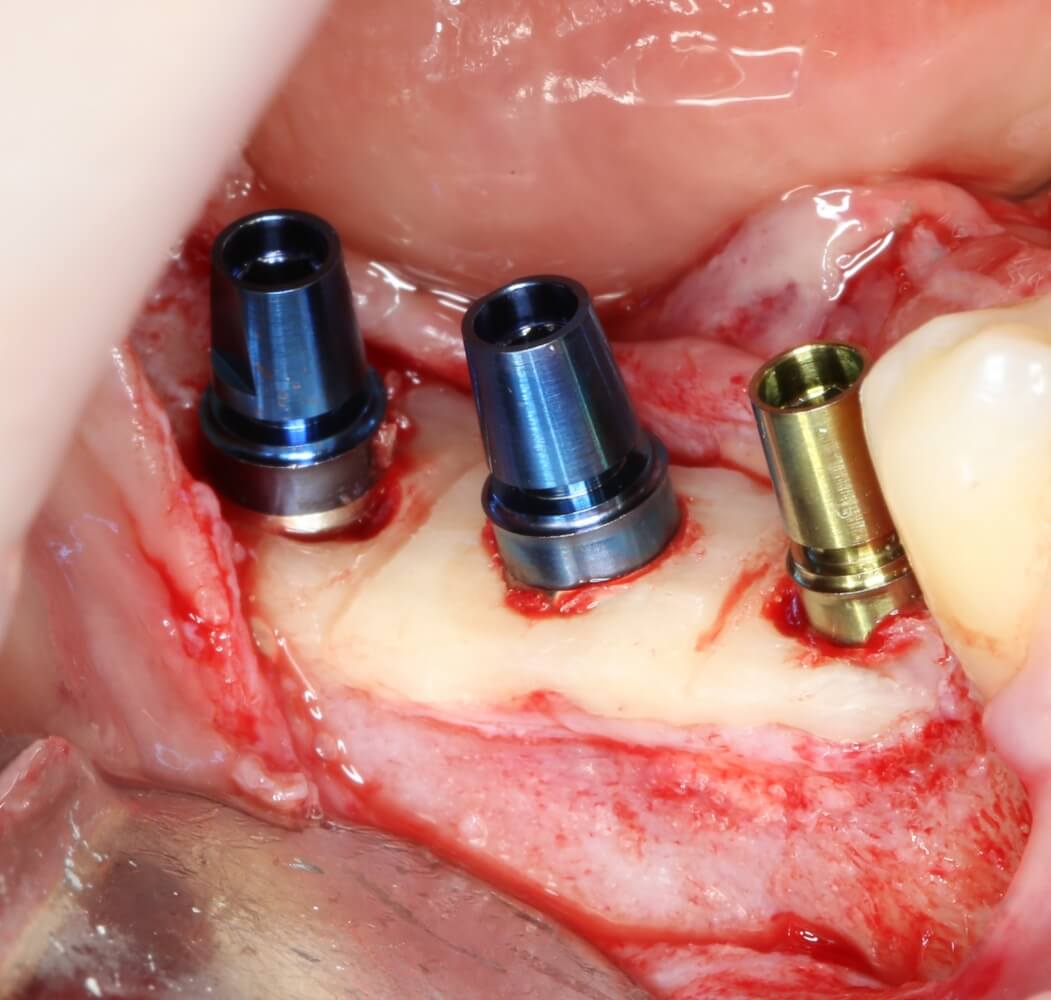

Установка имплантатов.

Напомню, что для этой работы я выбрал субкрестальные имплантаты Ankylos C/X. Они прекрасно сочетаются с любым методом остеопластики.

Я не планирую установку супраструктур или коронок, поэтому на уровень первичной стабильности можно положить болт. Даже наоборот — чем меньше крутящий момент при установке, тем лучше. Для имплантатов Ankylos и подобных им, это особенно важно. В общем, момент силы при установке — не более 10-15 Нсм.

Ремарка: имплантаты с предустановленными имплантодержателями хороши тем, что с ними легко контролировать позиционирование имплантатов. В случае с Ankylos С/Х - еще и крутящий момент. Имплантодержатель должен отсоединяться от имплантата с легким щелчком. Если его клинит, и тебе приходится прикладывать для этого усилия, то ты, однозначно, превысил момент силы во время установки имплантата. Следовательно, жди проблем.

Глянем на то, что получилось:

Осталось адаптировать костный блок (убрать острые края), проверить его фиксацию и, при необходимости, добавить винты. Десятисекундное дело.